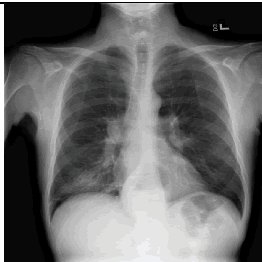

우리에게 굉장히 적은 데이터들이 주어졌을 때, supervised learning을 적용한다면 흔히 overfitting 문제가 발생할 것입니다. 예를 들어, 우리에게 아래와 같은 Chest X-Ray 폐렴 데이터만 갖고 있다고 해보겠습니다.

이미지 출처:https://www.openaccessjournals.com/articles/advanced-neural-network-solution-for-detection-of-lung-pathology-and-foreign-body-on-chest-plain-radiographs-13104.html

그림 출처:https://www.openaccessjournals.com/articles/advanced-neural-network-solution-for-detection-of-lung-pathology-and-foreign-body-on-chest-plain-radiographs-13104.html

의사들이 보는 폐렴 증상은 분명 폐주위의 섬유화에 주목하겠지만, 딥러닝의 경우는 CAM(=Class Activation Map)을 통해 살펴보면 엉뚱한데주목하는 경향이 있습니다. 아래와 같이 엉뚱한 곳을 보는 이유폐렴 관련 데이터는 저런 부분들만 살펴봐도 분류가 가능했기 때문일 수 있습니다. 즉, 정답의 이유는 상관없이 "학습 데이터의 정답만 맞추면 된다"는 식인 것이죠.

하지만, 저런 artifacts와 같은 요소들이 없는 폐렴 데이터가 들어오면 곧 바로 틀려버립니다. 즉, supervsied learning 방식을 사용한 CNN적은 수 의 폐렴 데이터로 학습하게 되면, 폐렴 CXR 이미지를 제대로 representation 해줄 수 없게 된다고 이야기 할 수 있습니다.